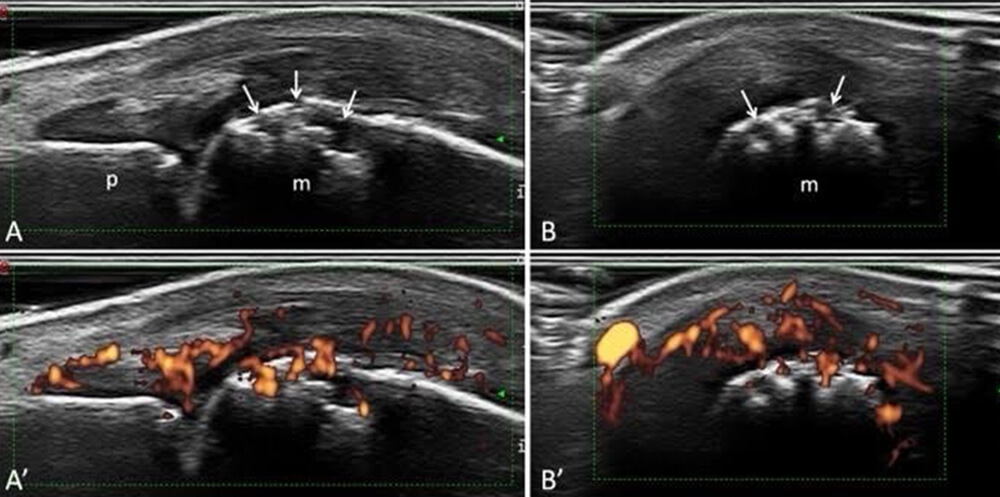

• エコー:滑膜炎の評価を簡便にできるので、診断や治療評価に有効です。

エコー